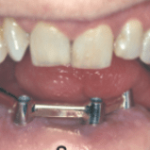

On the day of the surgery two surgical teams simultaneously resect the mandible and harvest the fibular graft using the previously printed stents, attach the reconstruction plate to the harvested fibular graft and then attach it to the remnant mandible; implants are placed there after using the stent. Following the implant placement there is a waiting period of 3-6 months for the graft to get accepted and implants to osseointegrate simultaneously.A prosthesis is then fabricated.

FIXED IMPLANT SUPPORTED PROSTHESIS WITH MULTIPLE IMPLANTS

Removable Prosthesis – necessitate fewer implants. The rehabilitation, follow up and oral hygiene are easier. The procedure is cheaper. It can also easily compensate for an aesthetic defect, especially in the anterior part of the mandible14

REMOVABLE IMPLANT SUPPORTED PROSTHESIS

The main problem with prosthesis remains the unfavourable implant–crown ratio and axis of the implants, which is not always the same as the axis of the prosthesis, leading to torque forces that may endanger implant survival.

The use of image-guided surgery and surgical guides decreases the risk and minimises the angulation between prosthetic axis and implant axis and also allows precise planning and accuracy of the rehabilitation15,16.

When placement of five implants or more is possible, a fixed ceramic prosthesis can be placed. A fixed hybrid ‘‘Branemark-like’’ prosthesis can be a good alternative for permanent rehabilitation. A bar framework

DENTAL PROSTHETIC REHABILITATION OF A CLASS III DEFECT WITH ORAL IMPLANTS IN THE FIBULA AND SUPRACONSTRUCTION USING A BAR-SUPPORTED DENTURE

can also be proposed for patients wearing a removable denture, as well as O-ring retained dentures or telescopic retention17.